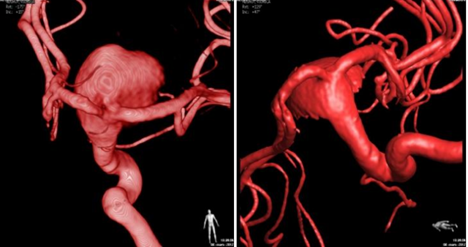

Exame de arteriografia cerebral com reconstrução tridimensional, melhor método de imagem para avaliação do aneurisma cerebral.

Para este procedimento, um neurorradiologista intervencionista realiza uma angiografia cerebral, idealmente com reconstrução 3D, para planejar o tratamento a ser realizado por via endovascular. Temos inúmeras técnicas para o tratamento, depende da localização, tamanho, morfologia, se já foi anteriormente tratado e do tamanho do colo “do pescoço do aneurisma”. Tais técnicas podem ser resumidas em 4: